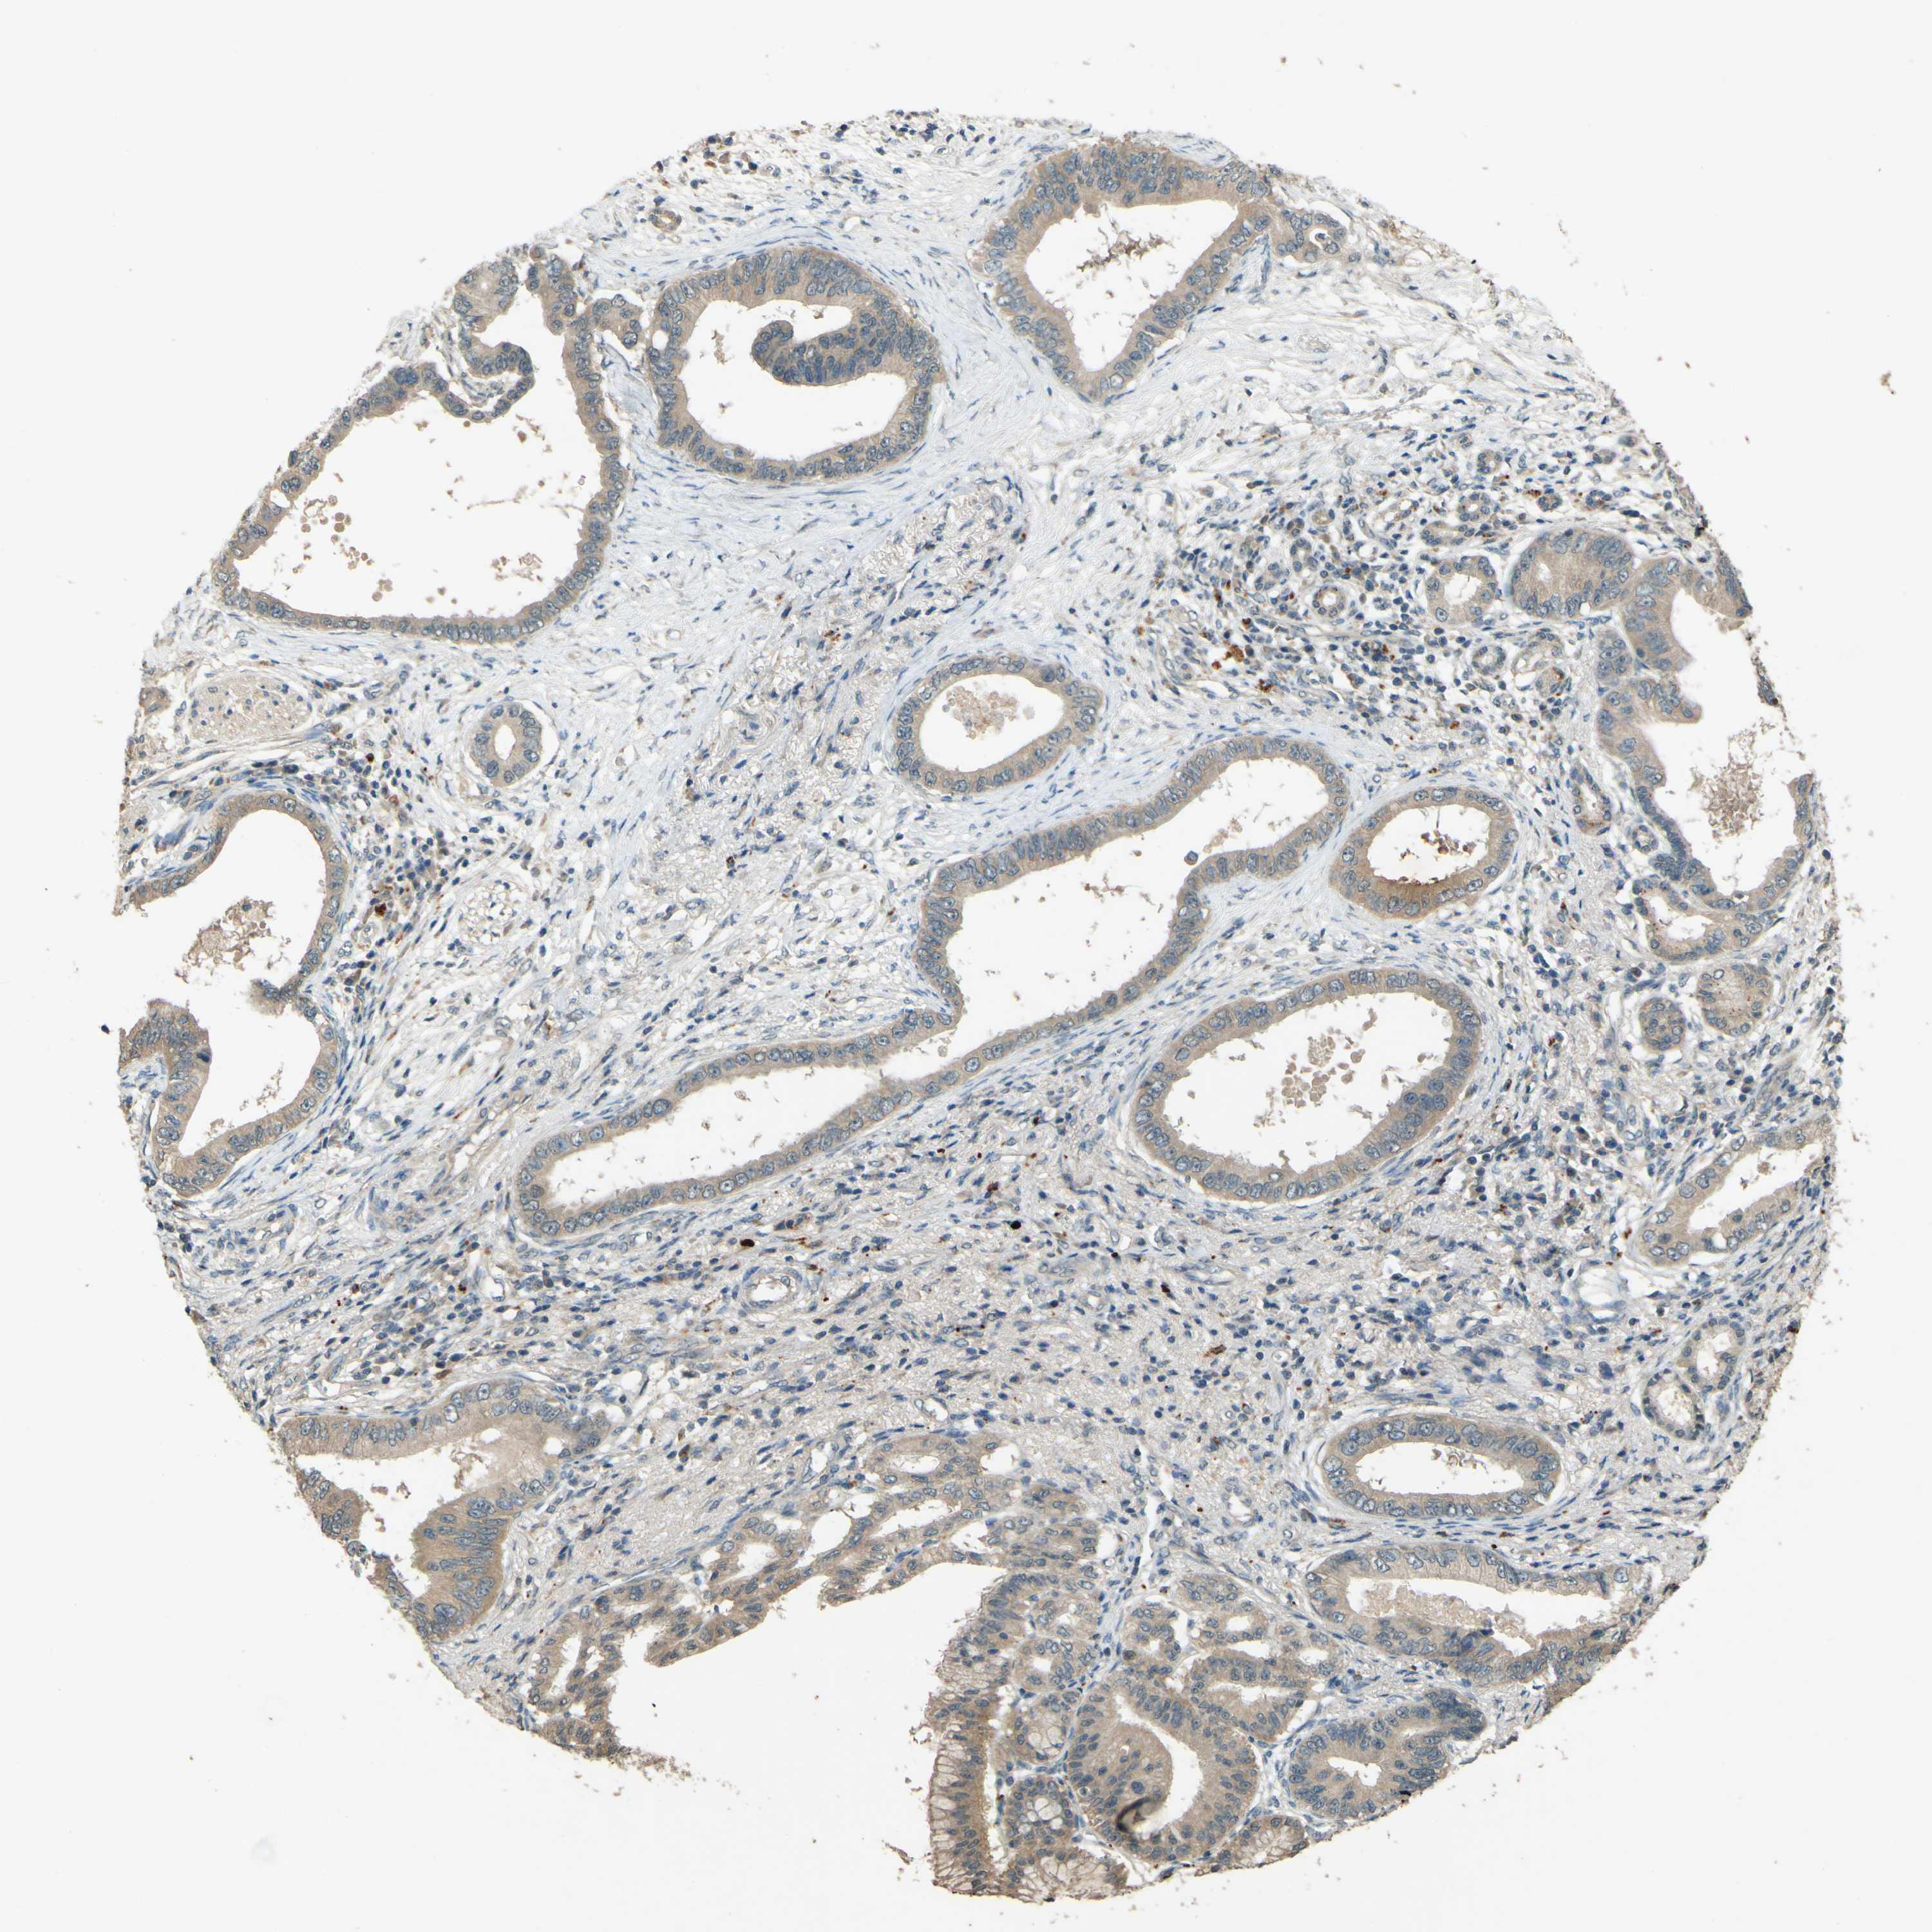

PANCREATIC CANCER - Protein expressioni

A mouse-over function shows sample information and annotation data. Click on an image to view it in a full screen mode. Samples can be filtered based on level of antibody staining by selecting one or several of the following categories: high, medium, low and not detected. The assay and annotation is described here.

Note that samples used for immunohistochemistry by the Human Protein Atlas do not correspond to samples in the TCGA dataset.

Antibody stainingi

Antibody staining in the annotated cell types in the current human tissue is reported as not detected, low, medium, or high, based on conventional immunohistochemistry profiling in selected tissues. This score is based on the combination of the staining intensity and fraction of stained cells.

Each image is clickable and will lead to virtual microscopy that enables deeper exploration of all samples and also displays staining intensity scores, fraction scores and subcellular localization as well as patient and tissue information for each sample.

Antibody HPA020255

Antibody HPA026686

Antibody CAB013512

Staining

High

Medium

Low

Not detected

Intensity

Strong

Moderate

Weak

Negative

Quantity

>75%

75%-25%

<25%

None

Location

Nuclear

Cytoplasmic/membranous

Cytoplasmic/membranous,nuclear

Adenocarcinoma, NOS

Adenocarcinoma, metastatic, NOS